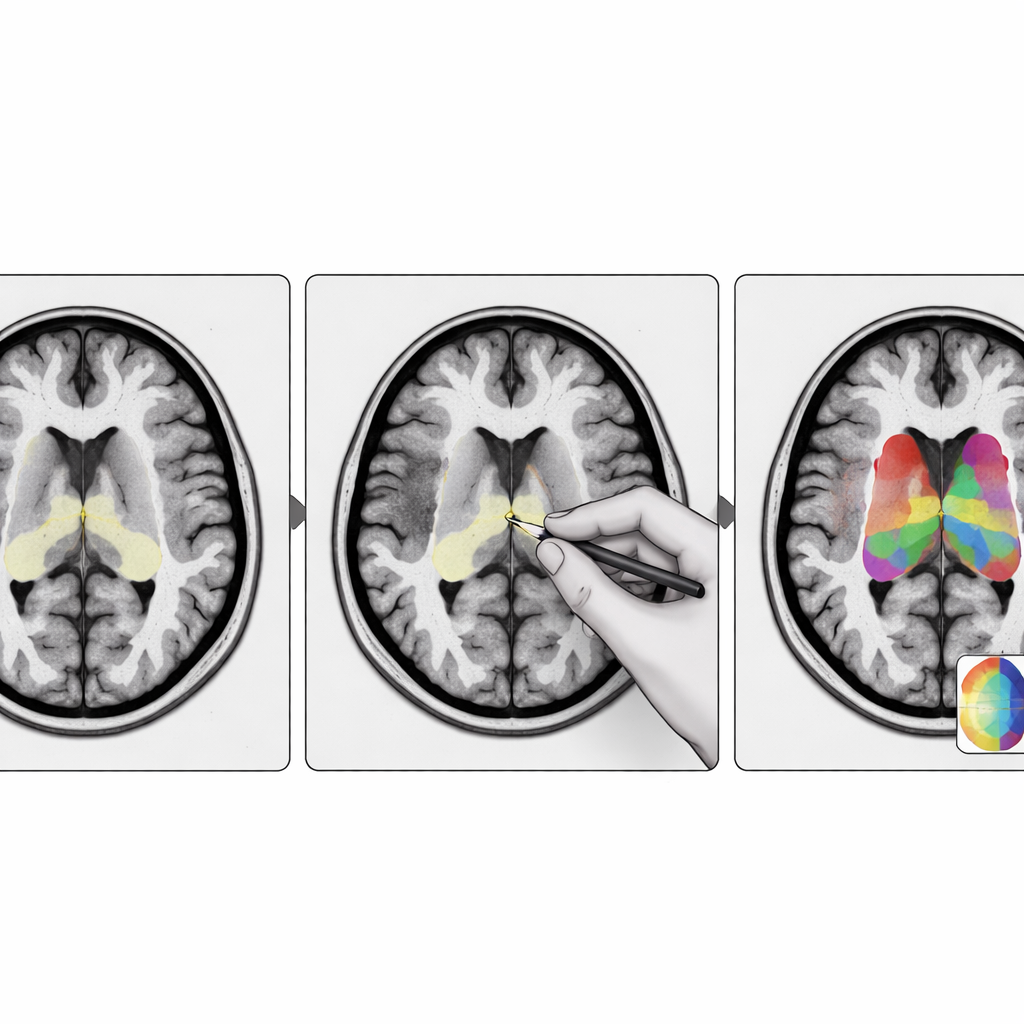

I ricercatori hanno progettato StriaSeg‑iARM come un sistema di deep learning in due fasi che lavora direttamente nello spazio cerebrale del singolo individuo anziché forzare la scansione in un modello standard. Nella prima fase il programma individua l’intero striato su una MRI tridimensionale. Nella seconda fase suddivide questa struttura in 12 sottoregioni definite anatomicamente su entrambi gli emisferi. Tra le due fasi sta l’innovazione chiave: un passaggio interattivo in cui un esperto può rapidamente verificare e, se necessario, correggere il contorno approssimativo prodotto dalla prima fase prima che venga eseguita la suddivisione più fine. Questo approccio combina la velocità dell’automazione con il giudizio di un osservatore umano formato.

Poiché l’obiettivo finale è quantificare i segnali PET, gli autori hanno anche esaminato come i diversi metodi di segmentazione influenzassero le letture PET. Utilizzando una misura standard del legame del tracciante in ciascuna sottoregione, hanno confrontato i risultati automatici con quelli basati su delineazioni manuali. Il metodo basato su atlante tendeva a sottostimare il legame, soprattutto nei pazienti con cambiamenti più severi, mentre il modello di deep learning di base mostrava ancora un bias evidente in alcune regioni. Al contrario, i modelli a cascata—soprattutto quando veniva usato il passaggio interattivo di correzione—producevano valori PET che seguivano da vicino il riferimento degli esperti, con bias e dispersione minimi. Il team ha inoltre dimostrato che un semplice punteggio di incertezza della prima fase può segnalare circa un quarto dei casi più difficili dove il raffinamento esperto è davvero necessario, lasciando il resto completamente automatico.